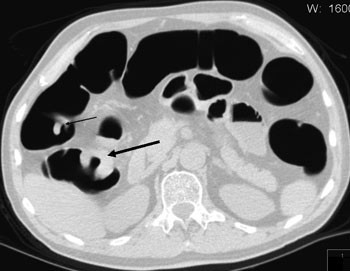

CT-kolografi synes å være spesielt godt egnet etter inkomplett koloskopi, helst utført samme dag. Pasienten vil i så fall allerede være forhåndstømt og ha en del gass i tykktarmen. Merbelastningen ved en CT-kolografi vil i så måte være beskjeden. I et materiale på 40 ufullstendige koloskopier ble det rapportert at CT-kolografi gav en fullstendig fremstilling av tykktarmen i over 90 % av tilfellene (31). Egne erfaringer som er gjort på denne type problemstilling, er også positive (fig 2). Når koloskopi er ufullstendig på grunn av strikturerende cancer, vil det kunne være hensiktsmessig at den supplerende CT-kolografiundersøkelsen utføres med tilpasset stråledose og intravenøs kontrast for eventuelt å påvise metastaser til lever og abdominale lymfeknuter.